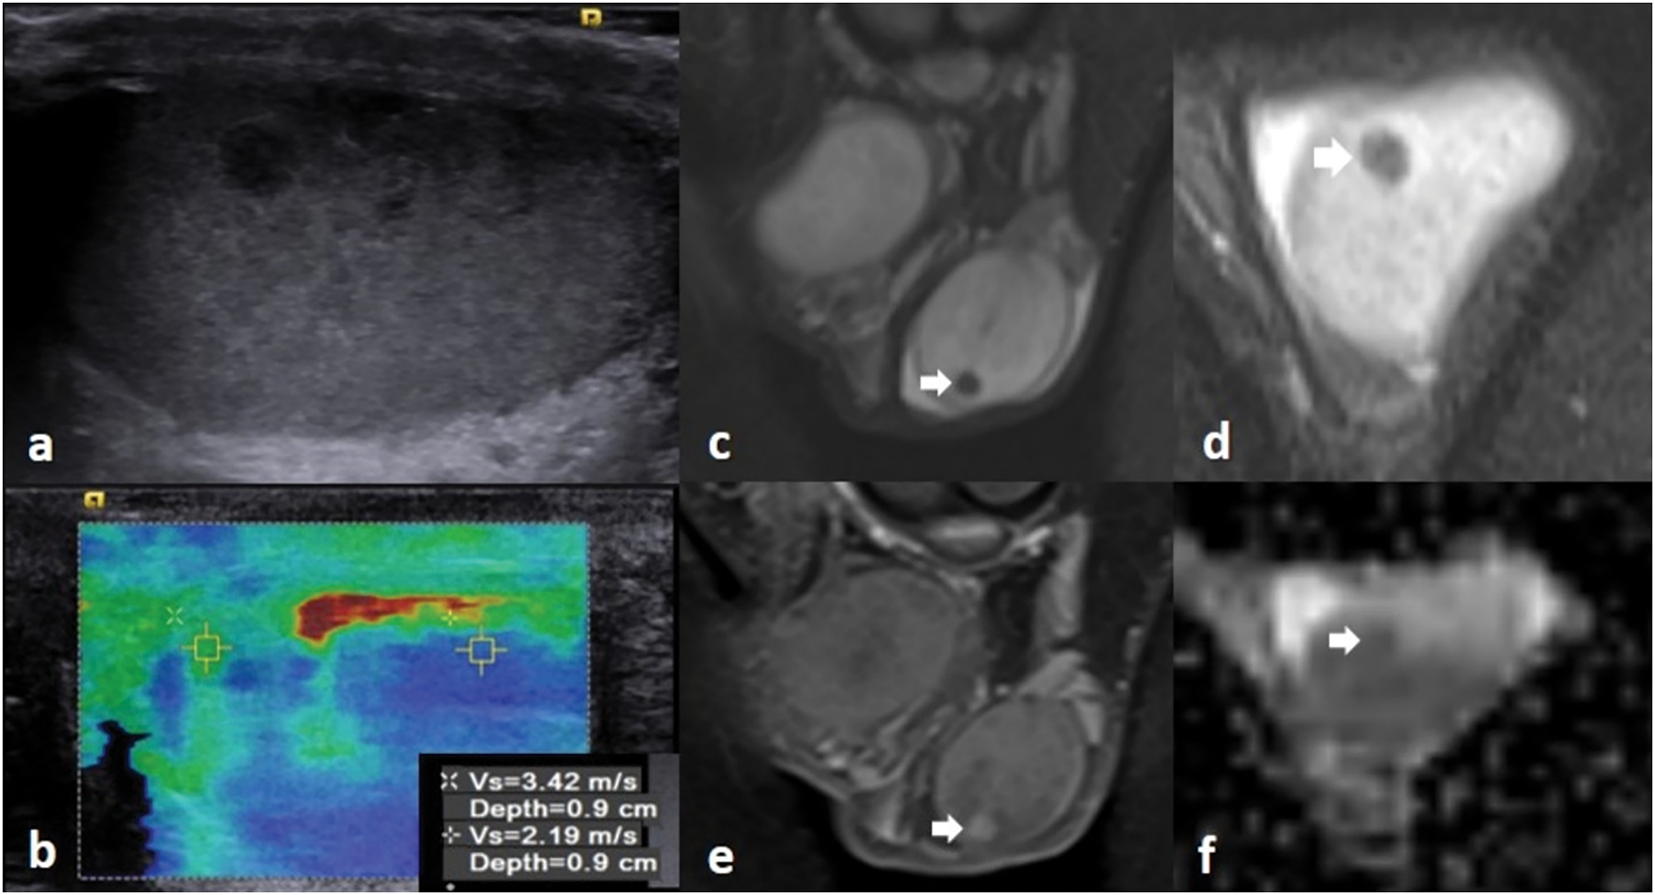

FIGURE 2. MRI images of a 34-year-old patient. (a) There is a 5 mm hypoechoic nonvascular solid lesion in B mode ultrasonography, which was observed to be harder than the normal testicular parenchyma in (b) ultrasound elastography images (pathology report: seminoma). (c,d) The lesion (white arrow) appears hypointense on T2-weighted images. The lesion (white arrow) enhanced on (e) postcontrast fat-suppressed T1 image, and it appears hypointense on (f) the ADC map, restricting diffusion

During the testicular ultrasound, the patients lie in the supine position. Patients are instructed to position the penis superiorly, and draping is used for privacy. Patients are primarily evaluated by gray scale (B-mode) examination. The echogenicity of the lesion relative to the testicular tissue, edge characteristics, presence of calcifications and cystic areas, and dimensions are described in detail in the report. The longest dimensions are specified in all three axes (TR × AP × CC). Blood supply is evaluated with color Doppler ultrasound. Elastography examination is performed in cases with difficulty in diagnosis, and stiffness rates are calculated compared to normal testicular tissue (Figure 1). Testicular MRI imaging is recommended for patients who still cannot reach a result (Figure 2).